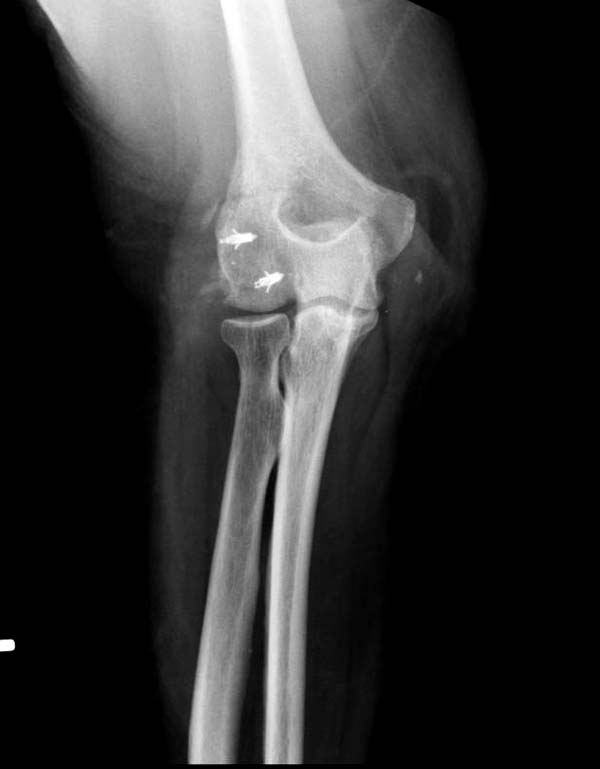

Снимки: 1-2 вывих, 4-5 вторичное смещение в гипсе, реконструкция

латеральной связки и капсулы 13-14, повторный вывих после реконструкции,

Вложение не в текстовом формате было извлечено…

Имя     : 5 Elbow dislocation postreduction.jpg

Описание: отсутствует